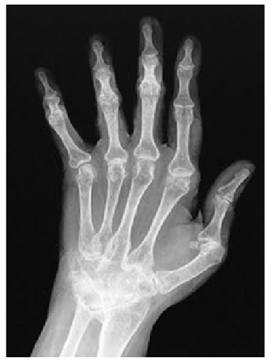

Table 5. X-ray Images.

X-ray 1X-ray 2X-ray 3X-ray 4X-ray 5

Mathematics 10 02421 i004 Mathematics 10 02421 i005 Mathematics 10 02421 i006 Mathematics 10 02421 i007 Mathematics 10 02421 i008

For the purpose of simulation, we consider two sets of images: (1) three images from MATLAB repository (Table 4) and (2) five X-ray images available online (Table 5).